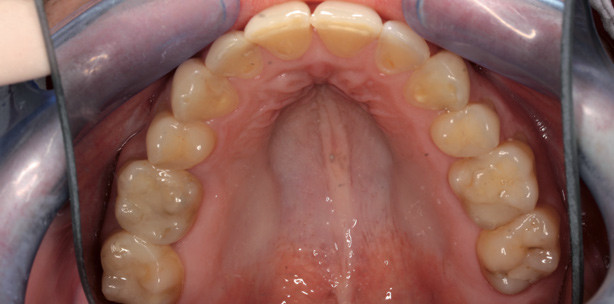

Der 36-jährige Patient stellte sich vor mit dem Wunsch nach Korrektur des Kreuzbisses. In­traoral zeigte sich ein fast zir­kulärer Kreuzbiss. Die Molaren waren noch neutral verzahnt. Der Zahn 14 wurde in der Jugend vermutlich aus Platzgründen extrahiert. In beiden Zahnbögen lagen leichte Engstände vor. Die OK-Mitte war nach rechts verschoben, die UK-Mitte wich mandibulär nach links ab. Skelettal lag sagittal nur eine leichte Angle-Klasse III vor (ANB 1°). Die vertikale Konfi­guration war leicht hyperdivergent.

Aufgrund des vertikalen Gesichtsaufbaus und der mandibulären Mittenabweichung wurde die Entscheidung für eine kombiniert kieferorthopädisch-kieferchirurgische Behandlung getroffen. Zur dentalen Dekompensation der Dysgnathie wur­de der Zahn 25 extrahiert und eine individu­elle Lingualapparatur (IncognitoTM) eingegliedert. Nach Lückenschluss und Ausformen der Zahnbögen wurde mit bimaxillärer Osteotomie die Lagebeziehung der Kiefer harmonisiert. In der postoperativen Phase wur­de mit lingual getrage­nen Elastics und mithilfe des im Set-­up festgelegten Frontzahn­torques ein ausreichender vertikaler Frontzahnüberbiss eingestellt. Die aktive Behandlungszeit betrug 13 Monate.

Fall 2: Dentale Kompensation

Der 23-jährige Patient stellte sich vor mit dem Wunsch nach ästhetischer Verbesserung der Frontzähne. Intraoral zeigte sich ein Kreuzbiss des Zahnes 12. In beiden Zahnbögen lagen moderate Engstände vor. Die klinische und instrumentelle Funktions­analyse wies eine Diskrepanz zwischen zentrischer Okklusion und zentrischer Relation nach. Sagittal waren die skelettalen Verhältnisse eher harmonisch, vertikal die Kieferbasen leicht hyperdivergent. Aufgrund der eher harmonischen skelettalen Verhältnisse wurde die Entscheidung für eine dentale Kompensation oh­ne Extraktionen getroffen. Es wurde eine individuelle Lingualapparatur (IncognitoTM) ein­gegliedert. Die Expansion der Zahnbögen erfolgte über komprimierte Bögen. Im Unterkiefer wurde eine approximale Schmelzreduktion mit oszillierenden diamantierten Scheiben durchgeführt. Mit bukkal getragenen intermaxillären Elastics wurde ein stabiler vertikaler Frontzahnüberbiss erreicht. Die aktive Behandlungszeit betrug neun Monate.